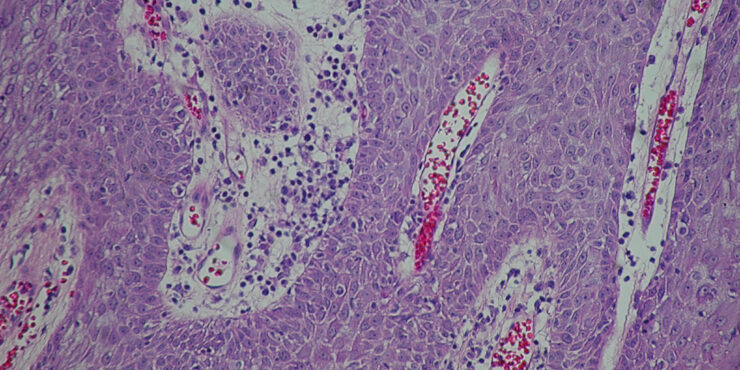

Read MoreSebaceous carcinoma = الكارسينوما الدهنية OLYMPUS DIGITAL CAMERA OLYMPUS DIGITAL CAMERA OLYMPUS DIGITAL CAMERA OLYMPUS DIGITAL CAMERA OLYMPUS DIGITAL CAMERA